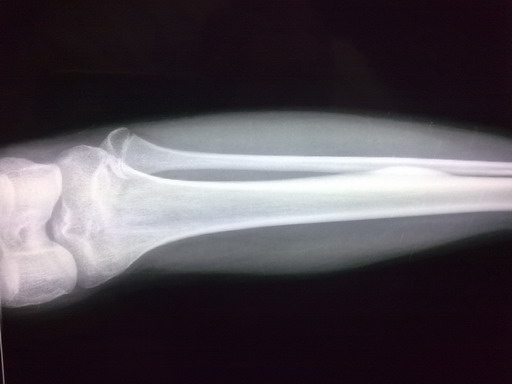

女孩,14岁,小腿疼痛一周,局部隆起,质硬,无红肿热痛

你侧胫骨中段见块状骨性突起。边缘清,并见硬化。考虑骨软骨瘤。

胫骨骨干皮质梭形增厚,虽无瘤巢,也考虑骨样骨瘤,原因不明,可能与感染有关,服用水杨酸制剂看看。

鉴别:骨化性纤维瘤、骨瘤、慢性骨膜下脓肿。

你侧胫骨中段见块状骨性突起。边缘清,考虑骨样骨瘤

左胫骨中段内前方骨皮质梭形增厚,髓腔未见累及,无骨膜反应。考虑良性病变。我考虑1低毒感染。

2骨样骨瘤:骨硬化较重,可能包埋了“瘤巢”。不象的地方就是病史不太支持:病程比较短,症状比较轻。试服用水杨酸制剂看看。

侧胫骨中段见块状骨性突起。边缘清,并见硬化。考虑骨软骨瘤。

考虑左胫骨中段骨样骨瘤。

左胫骨中段骨样骨瘤可能。隔期观察。

考虑 左胫骨中段骨样骨瘤。

考虑骨样骨瘤。病灶内部结构显示不清,请调调ct窗宽窗位。